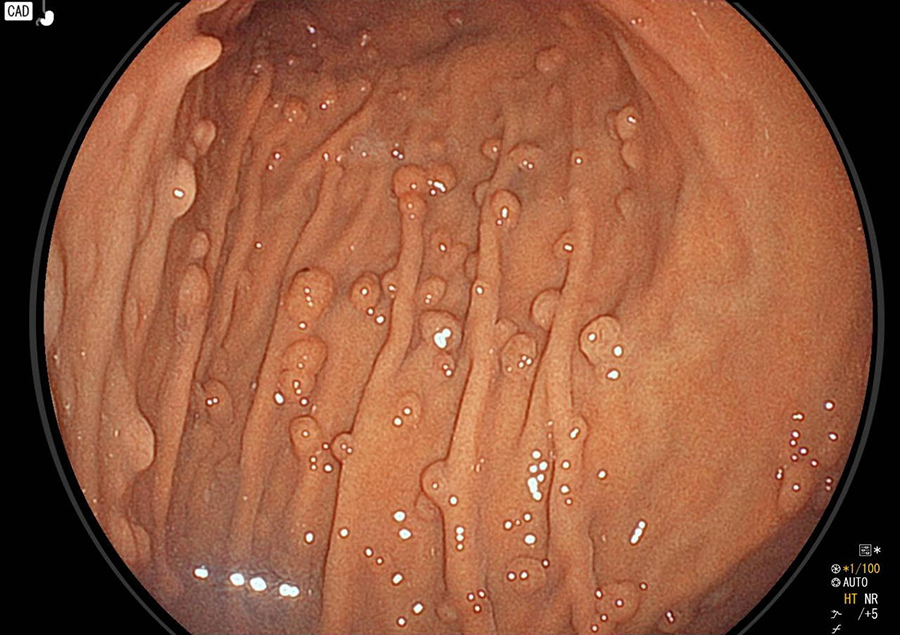

胃カメラ検査では、口又は鼻から内視鏡を挿入し、食道・胃・十二指腸の一部を観察します。直接胃や食道の粘膜を観察することができるので、色調や微妙な凹凸の変化が分かり、潰瘍・炎症・ポリープ・腫瘍などの診断が可能です。

胃カメラでわかる病気/病変

- 胃炎、ピロリ感染胃炎